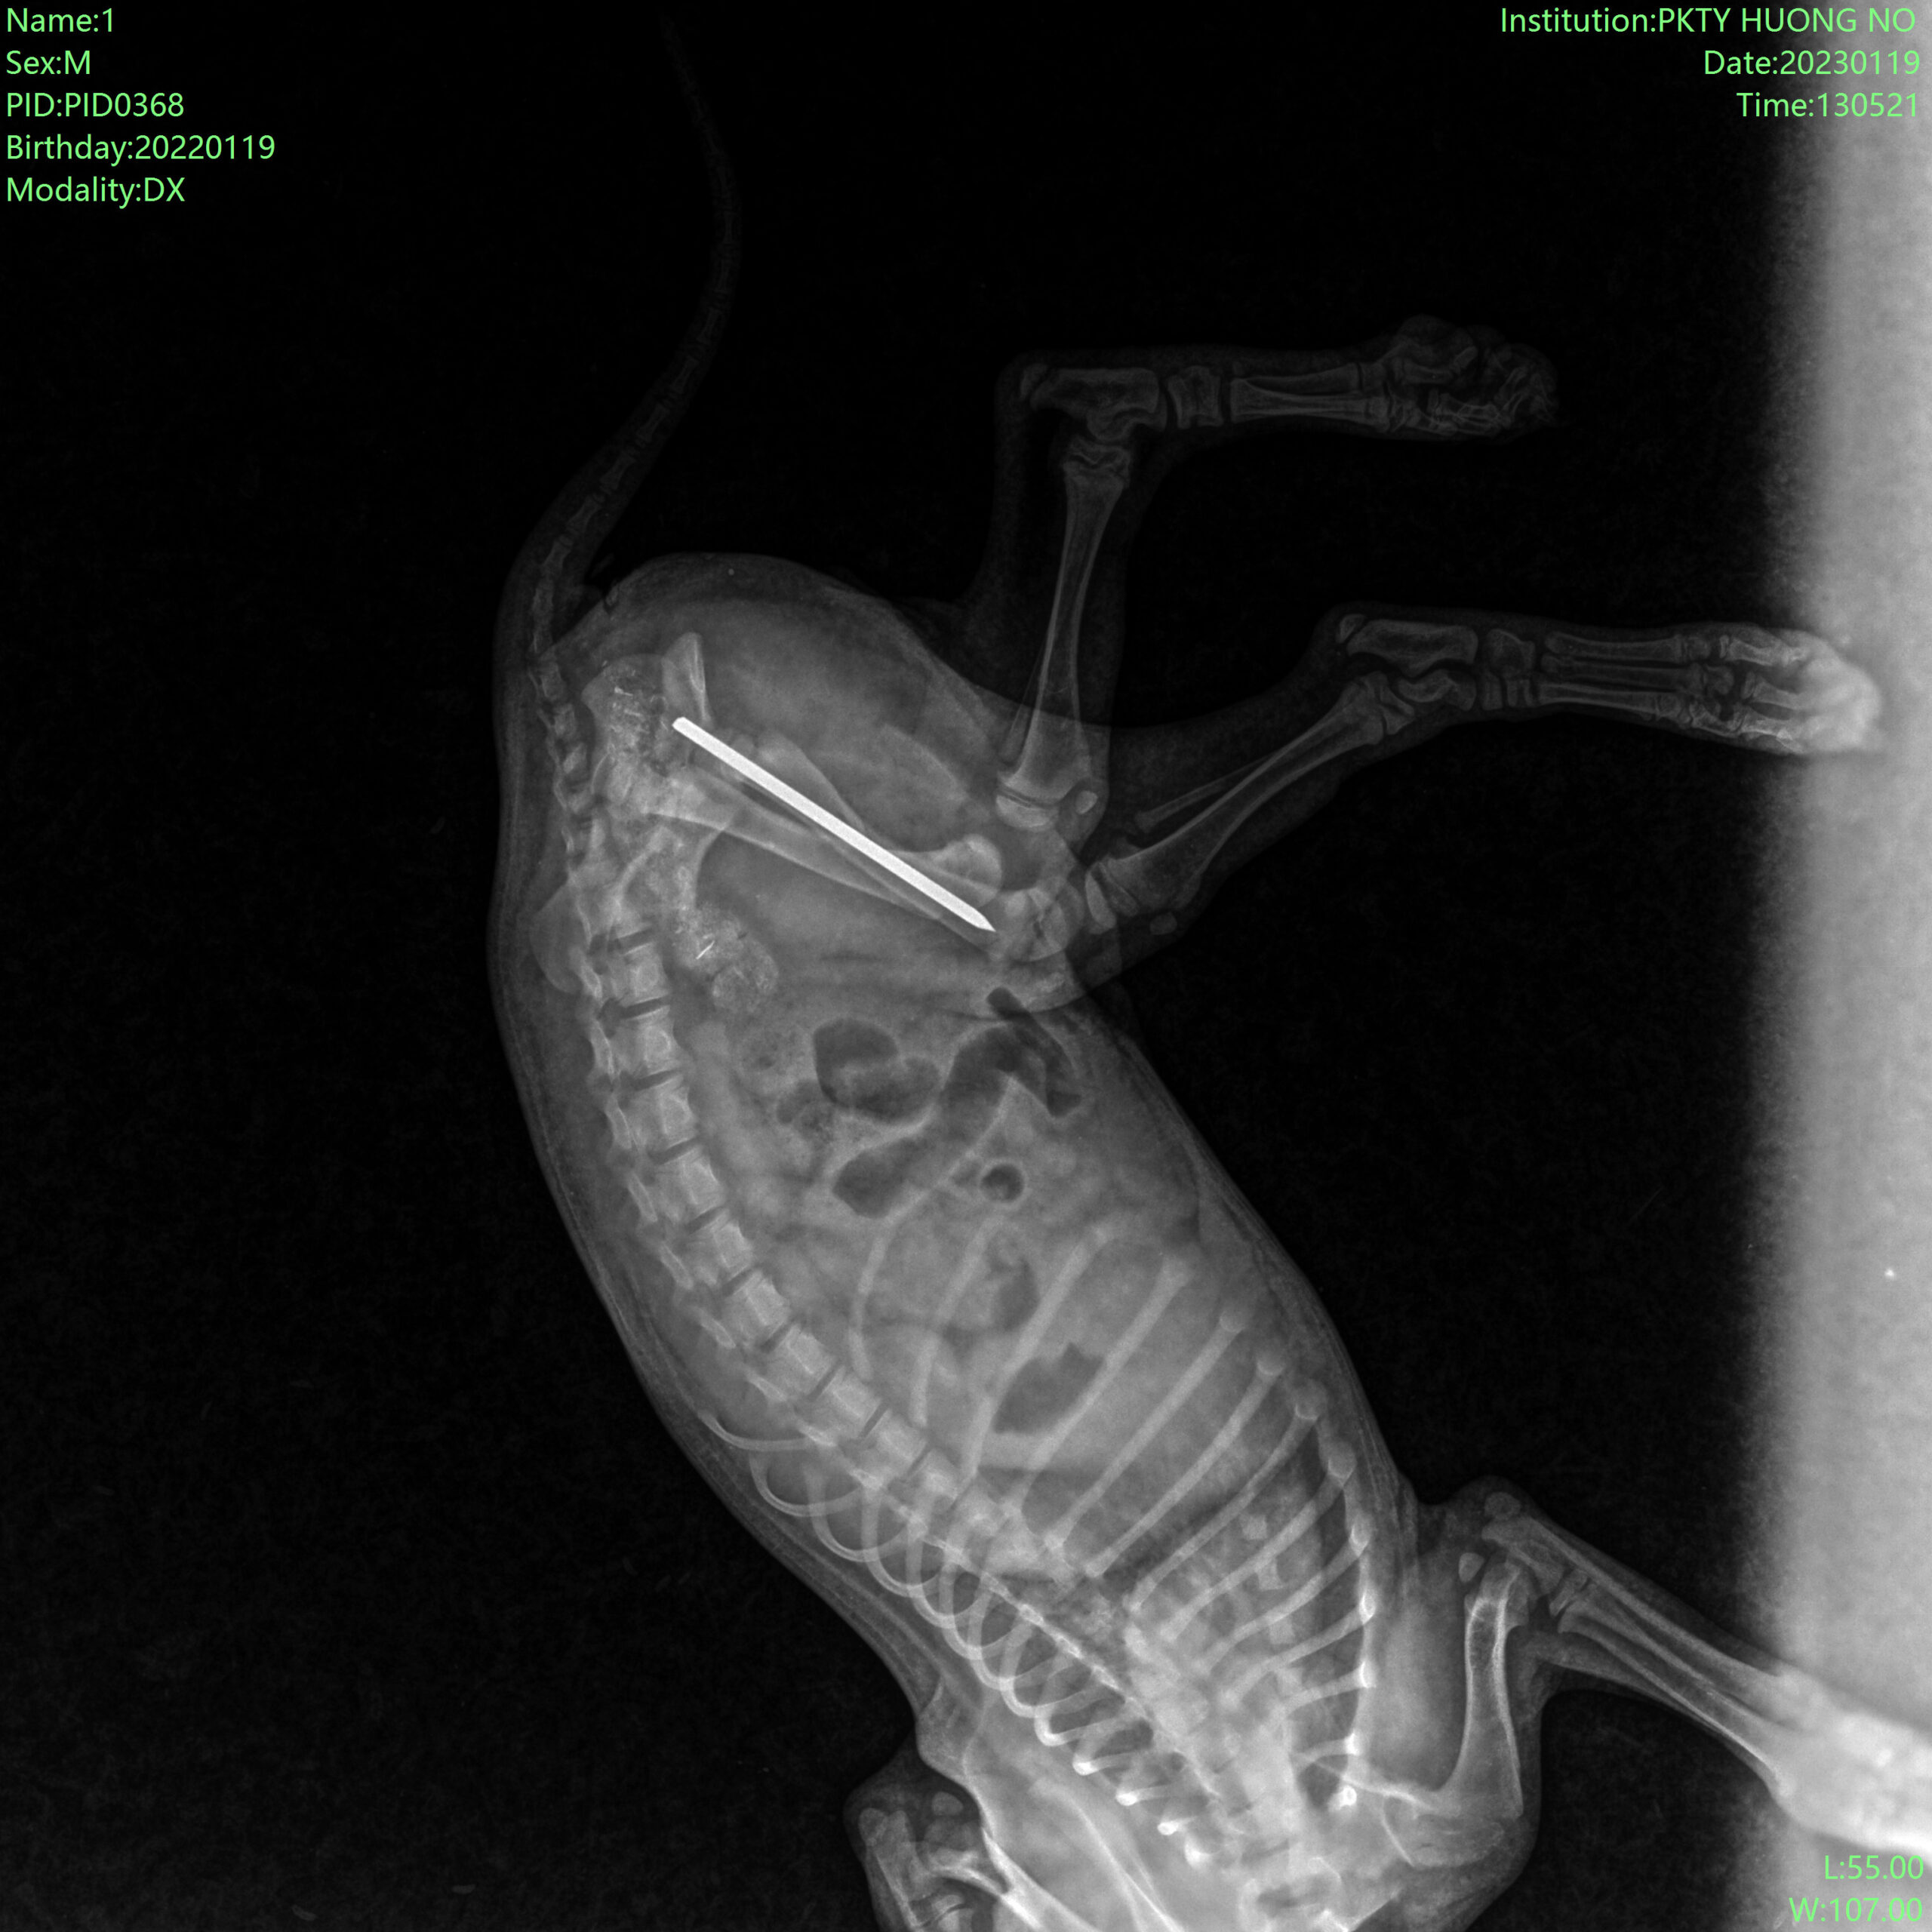

2. Ca ghép xương bé cún bị xe cán:

Sau phẫu thuật: